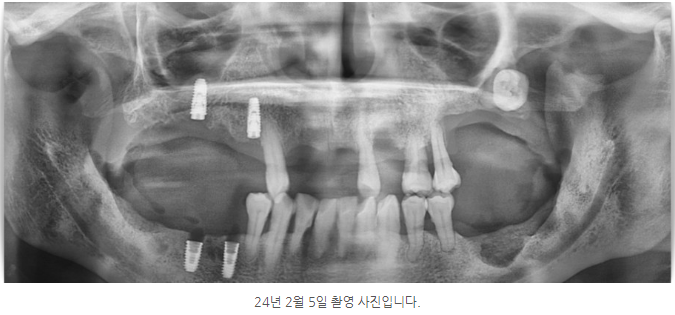

사진의 화살표 부위를 보면 위아래, 즉 수직 방향의 잇몸뼈 높이는 충분해 보입니다.

위 사진은 임플란트 식립 전과 후를 비교한 모습입니다.

다만 엑스레이 영상만으로는 잇몸의 폭이 넓은지, 좁은지를 정확히 판단하기는 어렵습니다.